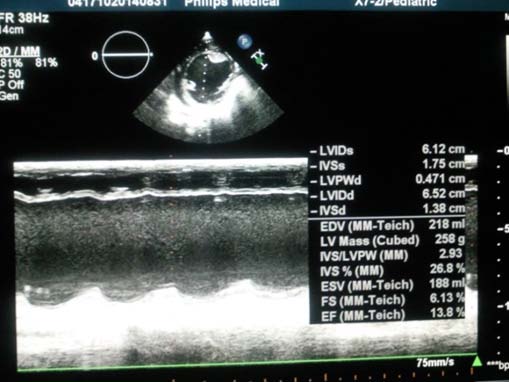

Case Relate: 6 months old girl admitted with symptoms of heart failure, Echo, ECG and Cath showed signs of ALCAPA with sever dilated cardiomyopathy. The baby sent for surgical repair, and direct implantation of the LCA into the ascending aorta was done successfully. The baby followed in our cardiology clinic monthly. After 6 month of surgical repair, the baby was good without any complain, all symptoms resolved, the Echo showed acceptable contractility and function, the dilated cardiomyopathy improved dramatically.

The Echo showed acceptable contractility and function, the dilated cardiomyopathy improved, EF became about normal EF = 52% (Figure 8).